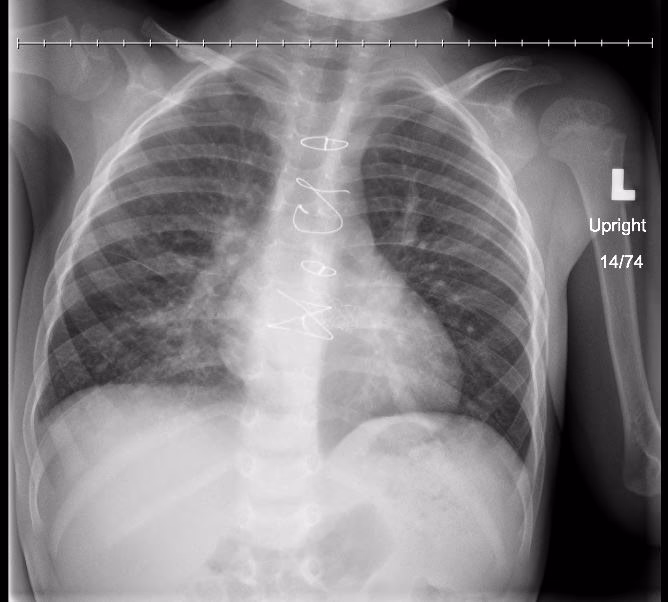

- Billeddiagnostik: Et røntgenbillede af brystkassen er ofte afgørende for at bekræfte diagnosen. Det kan vise de betændte områder i lungen (infiltrater) og give en idé om infektionens omfang.

| Røntgenbillede | Billeddannelse af brystkassen. | Kan visualisere betændte områder (infiltrater) i lungevævet. |